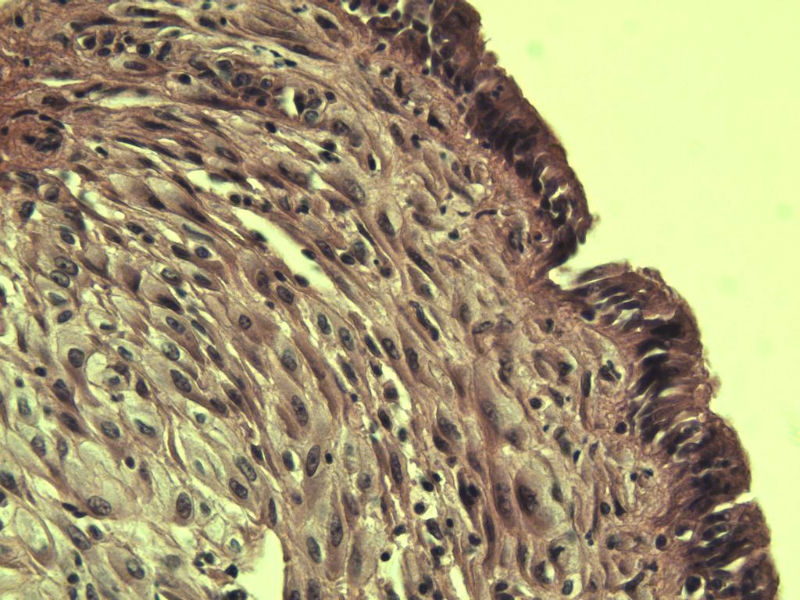

女 32岁 不规则阴道流血 一年  请各位老师看看 谢谢了

遵义医学院附属医院会诊结果    "复杂性增生伴非典型性 "

补充一下病史 病人10个月前因月经不规则行诊刮 诊断非典型性增生  上了曼月乐避孕环(好像是缓慢释放孕激素的那种),         都用激素治疗大半年了 还是这个样子 我还是觉得是癌  只有追踪一下以后病人的情况吧

高分化子宫内膜样癌

非典型复杂性子宫内膜增生,应了解雌孕激素情况。

子宫内膜复杂性非典型性增生,局灶区间质肉芽样(图5)及蜕膜样变,不够癌,建议临床查激素水平并追踪。

从照片看,没看到浸润的地方,我考虑是子宫内膜重度不典型增生。